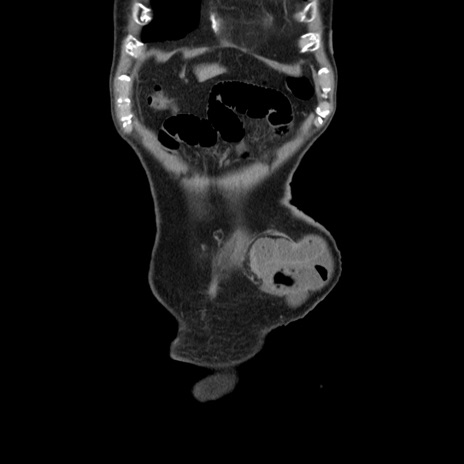

症例24(冠状断像)

【症例】80歳代男性

【主訴】左側腹部痛、嘔吐

【現病歴】本日早朝より左腹部に痛みあり。昼頃嘔吐認めたため、救急要請。

【既往歴】直腸癌(Mile手術)、胆摘

【身体所見】意識清明、BT 35.9℃、BP 221/93mmHg、SpO2 97%(RA) 、腹部:左ストーマ周囲に限局性の腹部膨隆あり。 膨隆部自発痛・圧痛あり・軟。

【データ】WBC 7700、CRP 0.09